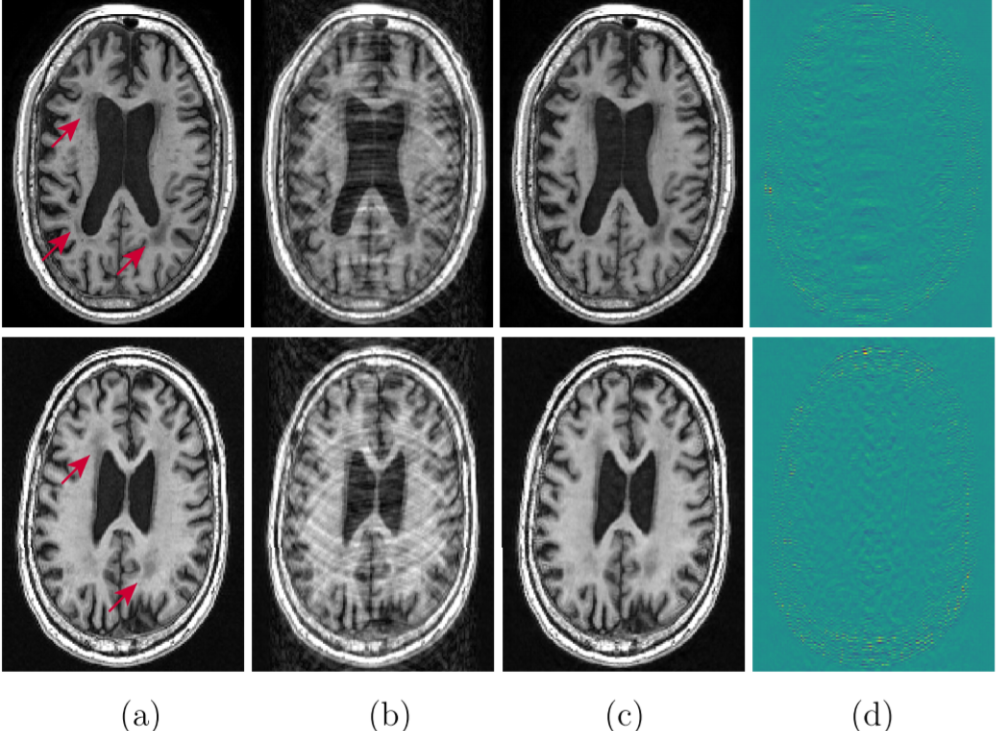

The accelerated magnetic resonance imaging (AMRI) by adversarial neural network method (Shitrit and Raviv, 2017) aims to generate the missing k-space lines, from using a conditional GAN, . The combined is Fourier transformed and passed to the discriminator. The AMRI method showed improved PSNR value with good reconstruction quality and no significant artifacts as shown in Fig. 4.

Later, in subsampled brain MRI reconstruction by generative adversarial neural networks method (SUBGAN) (Shaul et al., 2020), the authors discussed the importance of temporal context and how that mitigates the noise associated with the target’s movement. The UNet-based generator in SUBGAN takes three adjacent subsampled k-space slices taken at timestamps and provides the reconstructed image. The method achieved a performance boost of in PSNR with respect to the other state-of-the-art GAN methods while considering of the original k-space samples on IXI dataset (Rowland et al., 2004). We also show reconstruction quality of SUBGAN on fastMRI dataset in Fig. 5. Another method called multi-channel GAN (Zhang et al., 2018b) advocates the use raw of k-space measurements from all coils and has shown good k-space reconstruction and lower background noise compared to classical parallel imaging methods like GRAPPA and SPIRiT. However, we note that this method achieved dB lower PSNR than the GRAPPA and SPIRiT methods.